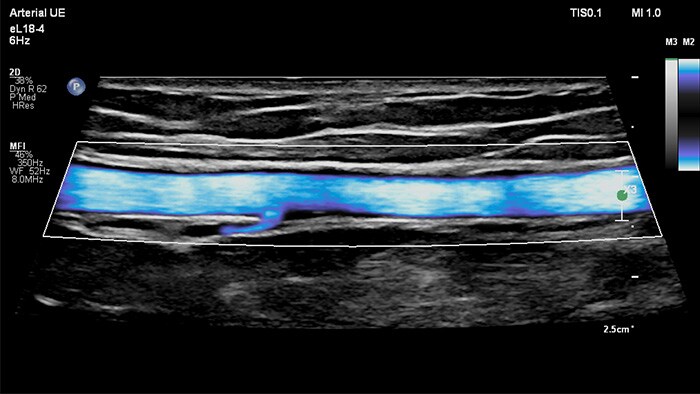

MicroFlow Imaging

MicroFlow Imaging de Philips se ha diseñado para identificar con una extraordinaria sensibilidad las zonas anatómicas que presentan un flujo sanguíneo lento y débil en los tejidos y, además, mejora la resolución del flujo en las exploraciones vasculares. Gracias a su alta resolución y cantidad mínima de artefactos, los profesionales sanitarios pueden visualizar y caracterizar alteraciones sutiles en el flujo alrededor de la placa estenótica para así elaborar diagnósticos fiables.